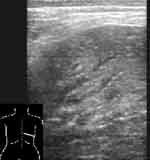

При снижении воздушности легочной ткани вследствие пневмонической инфильтрации или ателектаза, она становится эхографически видимой, имеет пониженную эхогенность и однородную эхоструктуру. Контур пневмонического очага в начале заболевания довольно ровный, форма может быть различной. В случае долевой пневмонии он повторяет форму доли, при сегментарной может иметь пирамидальную форму с основанием, обращенным к плевре, очаговой — неправильную, близкую к округлой. В безвоздушных пневмонических очагах бывают видны эхогенные, ветвящиеся, прерывистые полоски, являющиеся заполненными воздухом бронхами, а так же трубчатые анэхогенные структуры — сосуды или заполненные жидкостью бронхи и реже — тонкие линейные эхогенные полоски — соединительно-тканные межсегментарные перегородки (Рис. 2, 3). Эхогенная полоска плевры над безвоздушным участком (пневмоническим очагом или ателектазом) выглядит гораздо тоньше, чем над воздушным легким. Но это происходит не из-за «истончения плевры» [1], а из-за отсутствия составляющей отражения от поверхности воздушного легкого в комплексе плевральной эхогенной полоски. Пневмонические участки в наших наблюдениях имели несколько пониженную или среднюю эхогенность и не были гиперэхогенными, как указывают некоторые авторы [9, 2]. По мере же пневматизации при рассасывании инфильтрата в них появлялись множественные сливающиеся гиперэхогенные участки пневматизации. А высокая эхогенность при «свежих» пневмониях отмечалась за безвоздушными участками на границе с воздушной легочной тканью вследствие дистального усиления.

[Увеличить]

Рис. 2. Пневмонический очаг, содержащий эхогенные полоски воздуха в бронхах и тонкую межсегментарную перегородку.

Рис. 3. Пневмонический очаг с заполненными жидкостью бронхами.